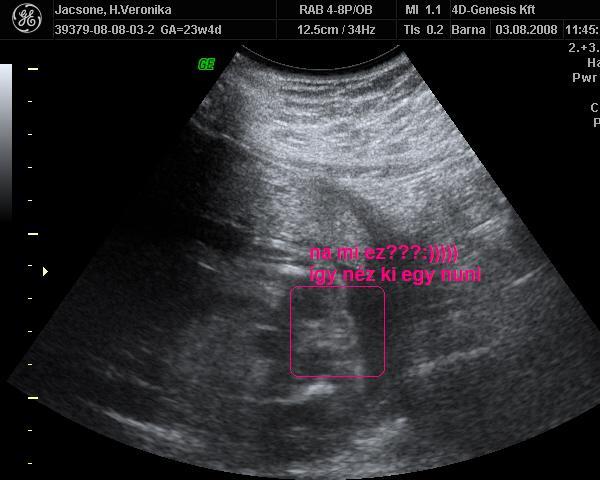

és kiderült valami tuti frankó :wink: :wink:

Kép

és itt van két kép az egyik fiamról. Mot róla készült.